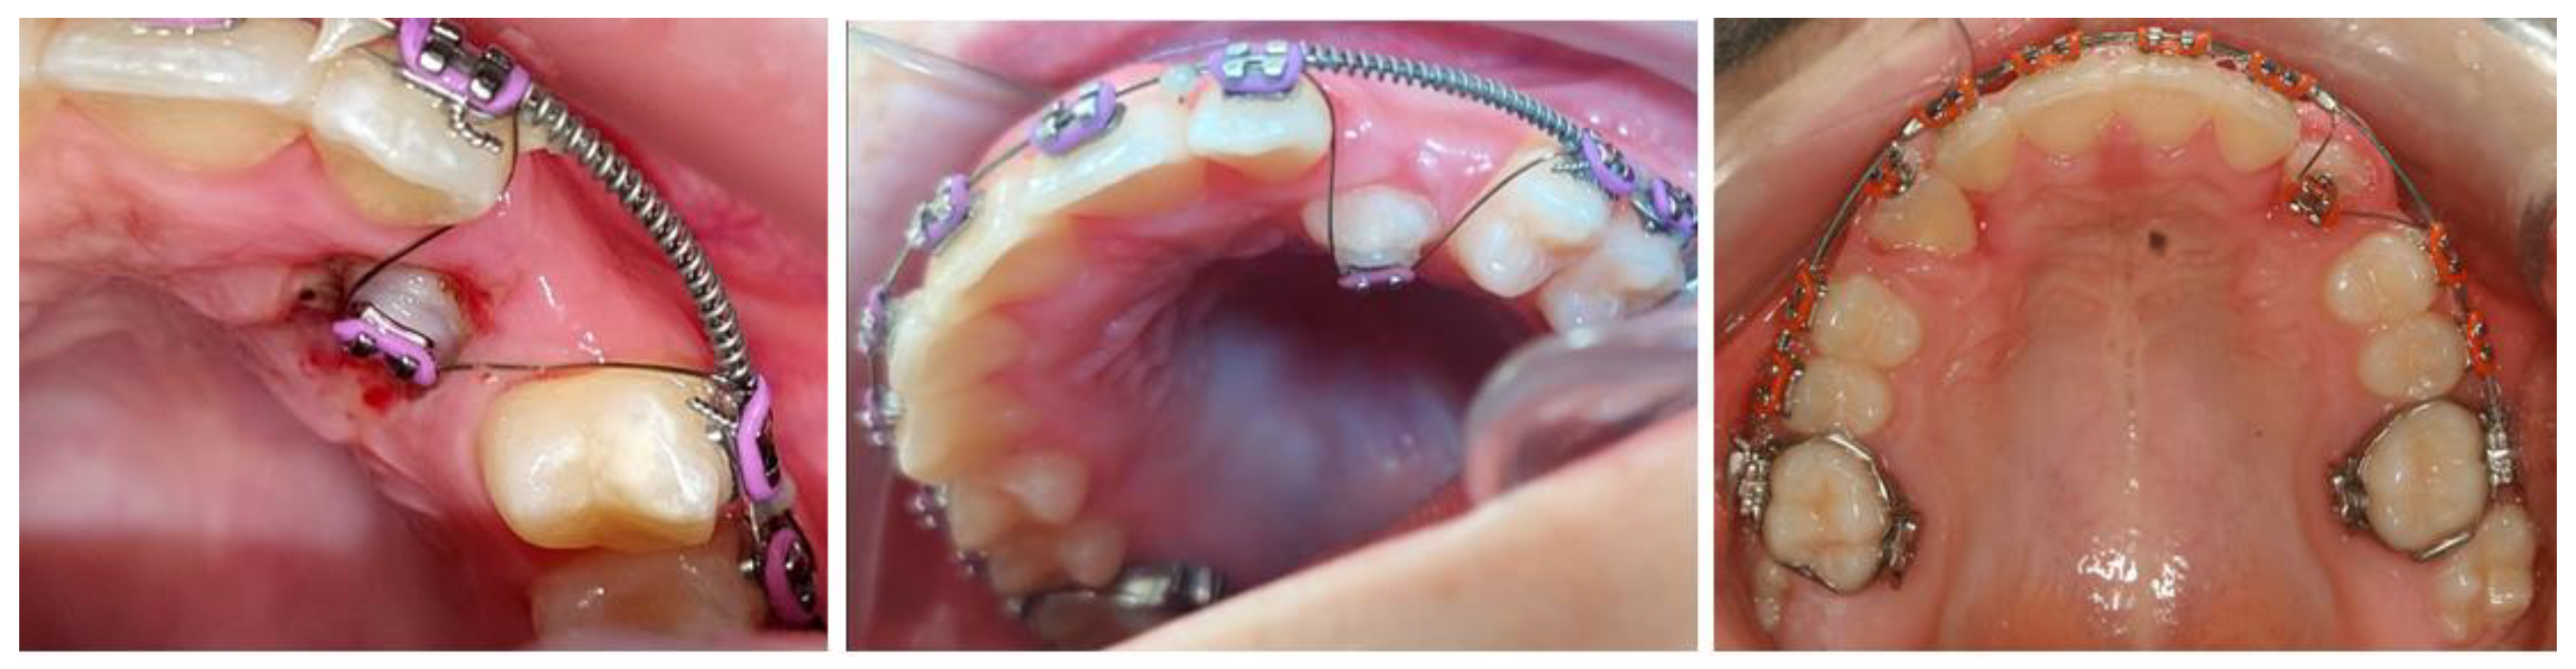

The double orthodontic wire consists of an additional 0.013-inch CuNiTi wire connected to the basal 0.019 × 0.025-inch NiTi wire (Figure 2). The 0.019 × 0.025-inch NiTi wire is the part that stabilizes the teeth in the upper dental arch after alignment, and the 0.013-inch CuNiTi superelastic wire is part of the active traction to move the maxillary impacted canines into the dental arch (Figure 2 and Figure 3).

In the SG, the bonded bracket was attached to the impacted maxillary canines with the ligature on the 0.013-inch CuNiTi orthodontic wire. The other part of the combined wire, the 0.019 × 0.025-inch NiTi wire, was inserted into the other upper brackets (Figure 3) to stabilize the teeth in the upper arch. The effect produced by the 0.013-inch CuNiTi wire is a summary of the properties of the wire itself and the geometric forces, and it actively tracks the impacted maxillary canine into its final position.

Figure 3. Double wire: the 0.019 × 0.025-inch NiTi wire was inserted into the brackets on the aligned maxillary teeth to stabilize them, and the 0.013-inch CuNiTi archwire was fixed with an elastic ligature in the bracket on the impacted maxillary canine to track it into the dental arch.